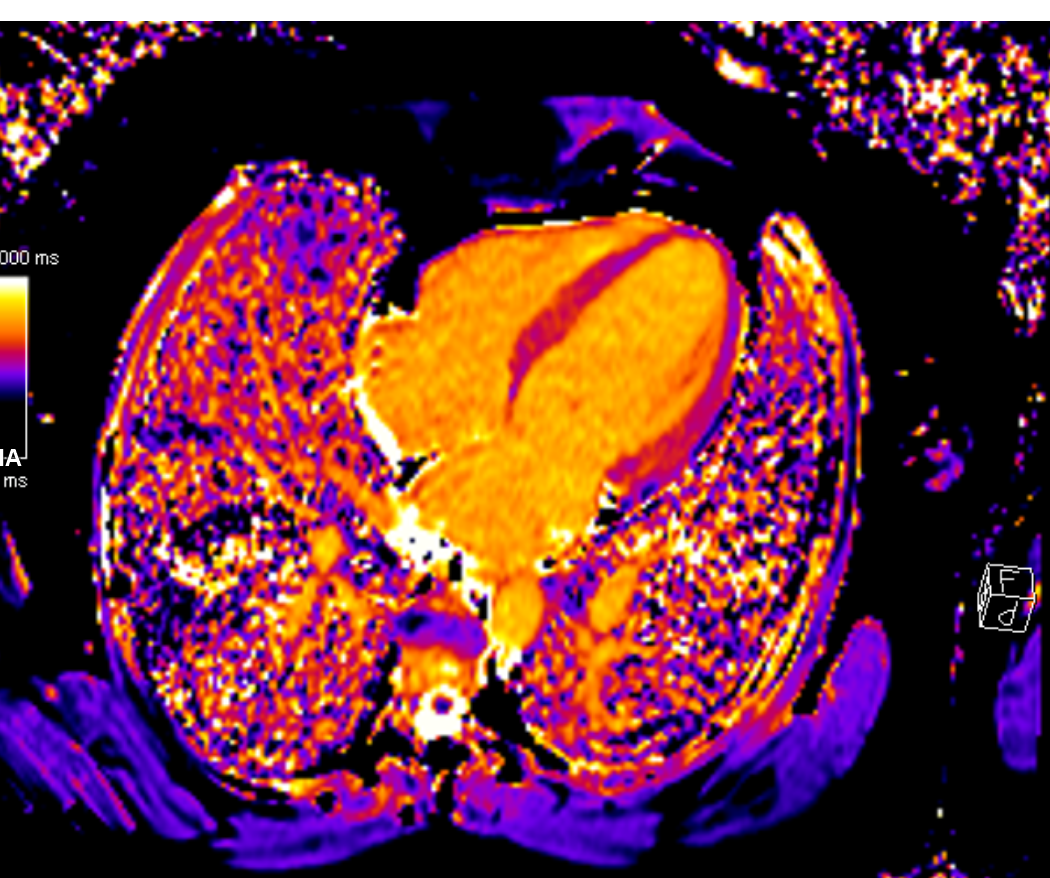

Η εικόνα είναι μια T1 mapping ακολουθία από μαγνητική τομογραφία καρδιάς (CMR T1 map) σε ασθενη με μυοκαρδιοπάθεια TAKOTSUBO